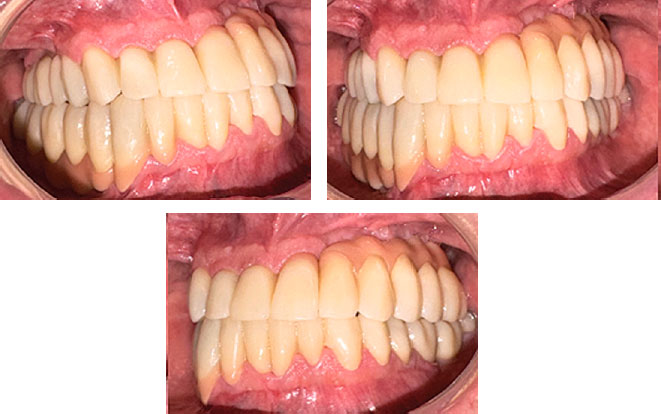

Фотографии окончательных протезов в полости рта (рис. 23).

Рис. 23. Окончательные протезы в полости рта

Fig. 23. Permanent restoration placement

За счет создания имитации розовой десны на циркониевых балках удалось камуфлировать наклон верхней челюсти, полученный в результате первичной дезинтеграции имплантатов (рис. 24).

Синдром вынужденного положения нижней челюсти проявляется совокупностью симптомов, требующих индивидуального подхода к диагностике и лечению [8, 9]. В статье представлен клинический случай поэтапного лечения пациента с синдромом вынужденного положения нижней челюсти с созданием 6 ключей окклюзии по Эндрюсу. В случае использования стандартного протокола протезирования по окончании лечения у пациента сохранилась привычная окклюзия с мезиальным соотношением зубных рядов и обратным резцовым перекрытием. Использование комплексного подхода повысило эффективность реабилитации пациента с данной патологией.